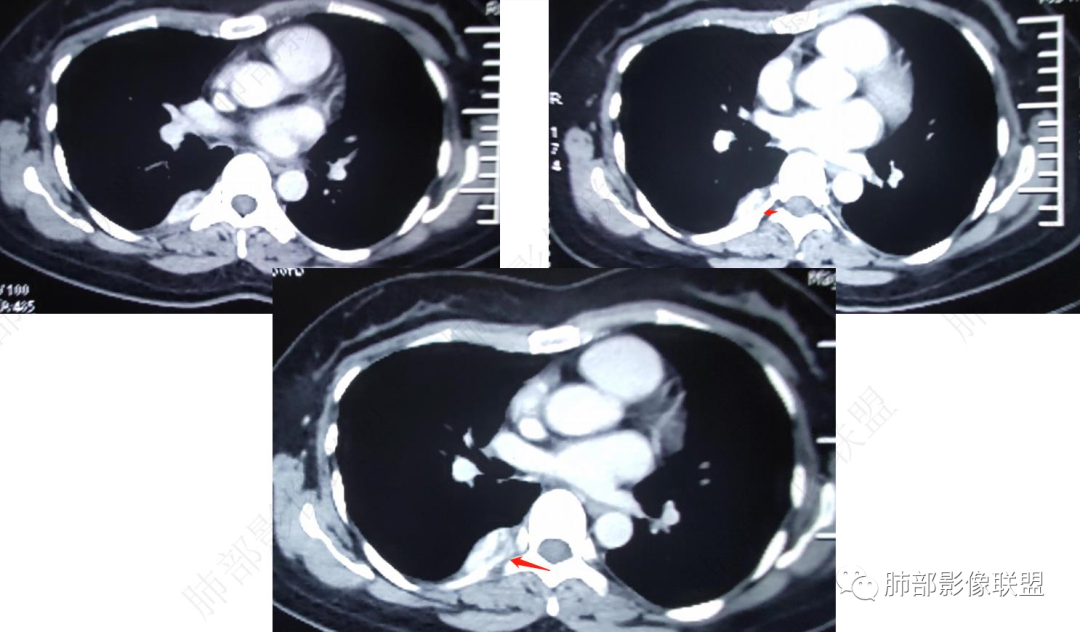

后纵隔不规则软组织密度影,强化方式和主动脉一直,考虑良性病变,血管畸形?

右上胸膜外脊柱旁可见梭形软组织密度影,边缘清晰,增强后呈血管样同步强化,MRI呈长T1、长T2信号影,信号均匀,似有尾征。考虑血管源性肿瘤,淋巴管瘤。

后纵隔胸椎右侧旁椭圆形软组织密度,密度均匀,未见囊变钙化等,临近椎间孔未见明显扩大,临近骨质未见异常,增强后显著渐进性强化,强化与主动脉一致。考虑血管瘤,鉴别副神经节瘤,神经鞘瘤。

后纵隔脊柱旁软组织密度影,边界清晰,密度均匀,增强扫描病灶与血管强化相仿,考虑血管瘤可能,鉴别神经源性肿瘤。

右后胸膜外明显强化结节,T2高亮信号,考虑血管瘤,监别神经鞘瘤,askin瘤

右后纵隔旁梭形占位,明显强化,与血管强化相似,压脂T2明显高信号,考虑血管源性肿瘤,血管瘤?

右侧脊柱旁沟明显强化结节,T2高亮信号,考虑血管瘤,鉴别神经鞘瘤。

肺外,明显强化,T2高信号,富血供,血管瘤,鉴别副节瘤。

后纵膈右侧胸膜外明显强化结节,T2明显高信号,考虑血管类肿瘤,血管瘤。鉴别神经鞘瘤。

右后脊柱旁可见梭形软组织密度影,边缘清晰,与胸壁关系密切,增强后呈血管样同步强化,MRI呈长T1、长T2信号影,信号均匀,高亮T2有点灯泡征的感觉,考虑血管瘤,鉴别神经鞘瘤

青年女性,后纵隔脊柱旁条形占位,边界清晰,T2高信号,增强后明显强化,考虑血管瘤

肺外,似乎胸膜尾征,动脉期和静脉期均明显均匀强化,T2高信号,排除sft,没有坏死,首先考虑血管瘤,年轻女性,鉴别髓外造血

脊柱旁病变,定位肺外,梭形,明显强化;核磁  T1等、T2高、压脂高亮信号,边缘清楚。考虑血管源瘤。

胸壁来源,胸膜位于病灶内侧缘,t2高亮信号,考虑符合血管及血窦,增强明显强化,与血管相仿,快进快出强化模式,说明血管通畅,考虑血管瘤,副节

CT表现: 大多数病灶呈境界清楚的肿块影,呈蔓状生长,质地软,仅少部分与周围结构分界不清,平扫时肿块密度均匀或不均匀,肿块内可见小点状钙化、静脉石或血栓形成,偶尔可见脂肪密度影,增强后强化方式多样,呈典型的多灶性或弥漫性不均匀性强化,也可呈中心型或外周型强化,肿块内也可见强化的血管腔,在动脉期即能显示与纵隔大血管一样的强化。

中青年女性,胸痛就诊,CT检查发现右后纵隔占位,病灶位于后胸壁纵隔移行区,略呈卵圆形或梭形蔓延,质地软,等/稍长T1、显著长T2信号,T2W脂肪抑制序列“亮灯”样高信号,这种磁共振信号特征对血管瘤具有强烈提示意义!(实在是太亮了,严格意义上的肿瘤罕见)

病灶显著强化,强化与纵隔大血管相仿且同期,一般会提示是血管源性病变,如血管瘤,如果边缘结节样强化逐渐填充渐进,则提示可能为海绵状血管瘤。